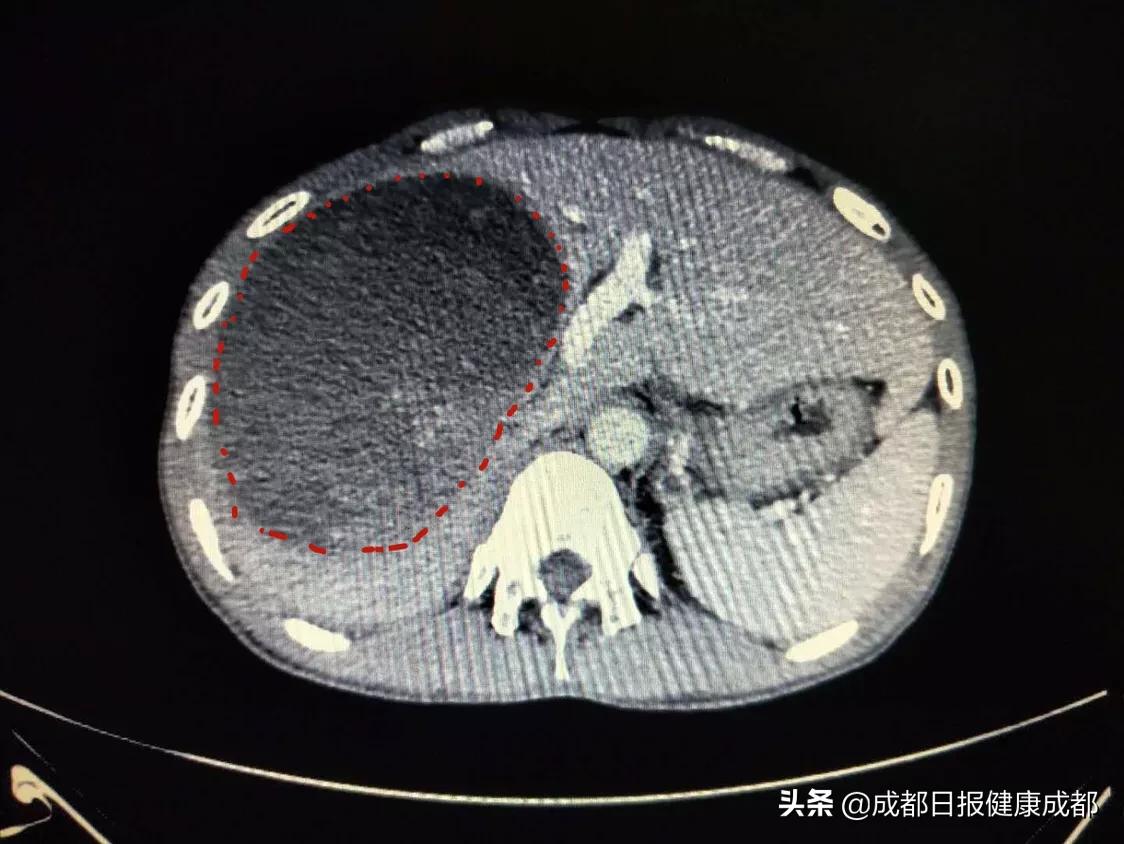

“肝脏上面长了一个巨大间质瘤,按体积推测至少已经有长了一年以上。”成都市第三人民医院普外科王明博士表示,罗阳在几年前就曾因为小肠间质瘤破裂出血接受手术治疗,但手术之后因为没按医嘱服药抗肿瘤复发的药物,极大提升了复发的概率,只是本次肿瘤长在了肝脏部位。因为肿瘤体积巨大,周遭的胃、十二指肠等脏器全部被挤压变形,进而出现了进食、呼吸困难等症状。

如果对肿瘤置之不理,一旦其破裂将导致扩散或大出血危急性命,尽快手术切除肿瘤是有效的治疗手段。幸运的是,经过进一步的检查,发现虽然肿瘤巨大,但仍旧有手术的机会。不过,虽然尚能手术治疗,但如何顺利开展手术却是一道难题——如果一口气切除被肿瘤浸润的肝脏,余下的部分将不足以支撑人体的正常运转。

经过多学科讨论,决定罗阳的手术通过分期的方式进行。首先,由放射介入团队以微创的方式,将肝脏右侧肿瘤周遭的滋养血管进行结扎。“这样一来,肿瘤和出问题的右侧肝脏就得不到养分供给。”王明表示,在肿瘤和问题右肝“缩水”的同时,健康的左边肝脏将迅速成长,待达到标准后即可开展手术。

经过一个月时间的“定向培养”,罗阳的左肝体积增长了30%,达到可以手术的标准。经过近5小时的精心手术,其肝脏上直径达20cm、重达4斤的巨大间质瘤得以顺利切除。新年将近,康复出院的罗阳还专门寄来家乡的橘子表达谢意。